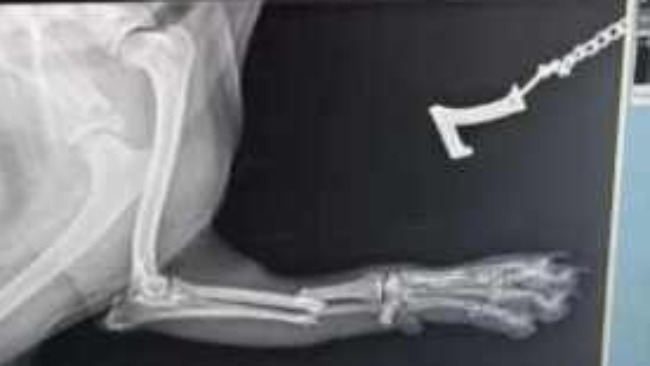

Koksik to czteroletni piesek, który trafił ze schroniska do wymarzonego kochającego domu. Niestety, los postawił przed nim nowe trudne wyzwania – uległ wypadkowi i doznał złamania przedniej lewej łapki. Właściciel niezwłocznie zapewnił mu leczenie, niestety przeprowadzona operacja nie przyniosła oczekiwanych rezultatów, a Koksik ma niewładną lewą łapkę.

Jesteśmy już po diagnozie i konsultacji chirurgicznej. W badaniu rtg w sedacji cechy obecności płyty kostnej, odłamy kostne niestabilne, wokół wkrętów odczyny zapalne oraz zanik kostny. Co znaczy, że jeżeli nie zoperujemy Koksika czeka go amputacja łapki.